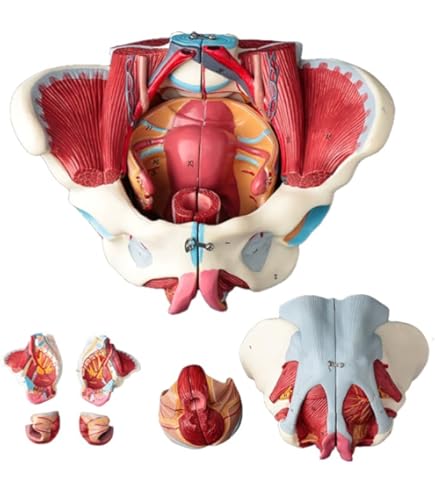

女性骨盤,内臓・骨盤底筋付,6分解モデル | 日本スリービー。Amazon.co.jp: 骨盤靭帯や骨盤底筋,骨盤内臓,血管や神経なども。女性骨盤,内臓・骨盤底筋付,6分解モデル | 日本スリービー。朝日 5キロ 令和6年産。●商品 : 【骨盤靭帯や骨盤底筋、骨盤内臓、血管や神経なども再現した女性骨盤模型の上級モデル、女性骨盤内臓・骨盤底筋付,6分解モデル - 3B Scientific】日本スリービー・サイエンティフィック株式会社の女性骨盤内臓,骨盤底筋,血管・神経なども観察できる女性骨盤模型です。③パラマウントベッド 楽匠 手元スイッチのみ リモコンのみ 2モーター 新楽匠。これからウィメンズヘルス分野などで開業、開院される方などにお勧めです。【美品】女性骨盤模型 6分解モデル 上級モデル 骨模型。骨盤底全体をあらわすモデルで,正中矢状断された外肛門括約筋,外尿道括約筋,深会陰横筋,浅会陰横筋,球海綿体筋は部分的に取り外し可能です。Littmann リットマン 聴診器。以下の部位を確認できます。幸和製作所 テイコブ 手押し車 ショッピングカー ST07 格子紺 ネイビー。右骨盤では以下の骨盤靭帯を確認できます。3B Scientific 女性骨盤モデル(可動型) ー 25300400 A61/1 1台。講義や母親学級で使用するために2021年2月にAmazonで購入しました。出向先に同じ物があり、こちらの私物を使うことが無いため、必要な方にお譲り致します。LITTMANN リットマン 聴診器 3M。ステート リットマン 聴診器。Amazonで2024年1月30日現在、156,200円で販売されている商品です。●商品詳細この女性骨盤6分解モデルは,骨盤・靭帯・血管・神経・骨盤底筋・女性骨盤内臓を再現しています。安寿 浴室 手すり アロン化成 高さ調節付浴槽手すりUST-130。高さ低めの 介護用車椅子。直腸,子宮(卵管・卵巣付),膣も取り外すことができ,正中矢状断で半分に分解可能です。右半分の骨盤では総腸骨動脈,内腸骨動脈,外腸骨動脈,総腸骨静脈,外腸骨静脈等の局所解剖を表しており,右仙骨神経叢,右坐骨神経,右陰部神経も確認できます。介護用歩行車、介護用歩行器、シルバーカー、歩行補助車、交互歩行器、介護用車椅子、。【未使用】トイレ用手すり 介護 サポート ホワイト TRT-64A。左右の寛骨恥骨結合仙骨尾骨椎間板付第5腰椎第5腰椎から仙骨・尾骨まで正中矢状断されているので骨盤を半分に分解可能で,脊柱管にある馬尾の一部も観察できます。第5腰椎の左半分は取り外し可能です。リットマン 聴診器 ステソスコープ。★入浴用キャリーベルト★介護。鼠径靱帯仙結節靱帯仙棘靱帯前仙腸靱帯腸腰靱帯前縦靱帯骨間仙腸靱帯後仙腸靱帯閉鎖膜カテゴリー: ダイエット・健康>>>自助具・リハビリ用品>>>その他 商品の状態: 未使用に近い 配送料の負担: 送料込み(出品者負担) 配送の方法: 佐川急便/日本郵便 発送元の地域: 福岡県 発送までの日数: 2~3日で発送 商品の詳細